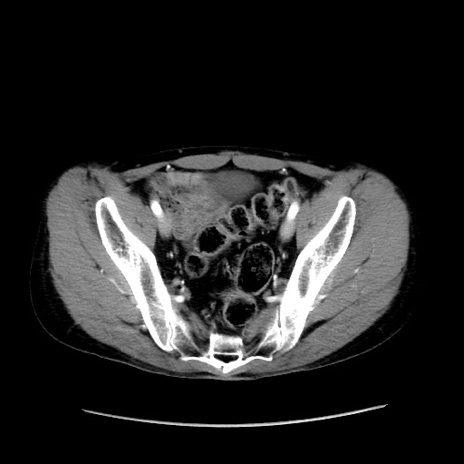

症例37(横断像)

【症例】40歳代 男性

【主訴】腹痛

【現病歴】4時間ほど前に電車に乗車中に臍部上より腹痛出現。徐々に増悪し起立困難となり、救急外来受診。生ものは数日食べていない。今朝お雑煮を食べた。

【身体所見】BT 36.8℃、BP 117/84mmHg、HR 91/min、SpO2 97%、苦悶様、腹部:臍上部広範囲圧痛あり、反跳痛±

【データ】WBC 8100、CRP 0.03